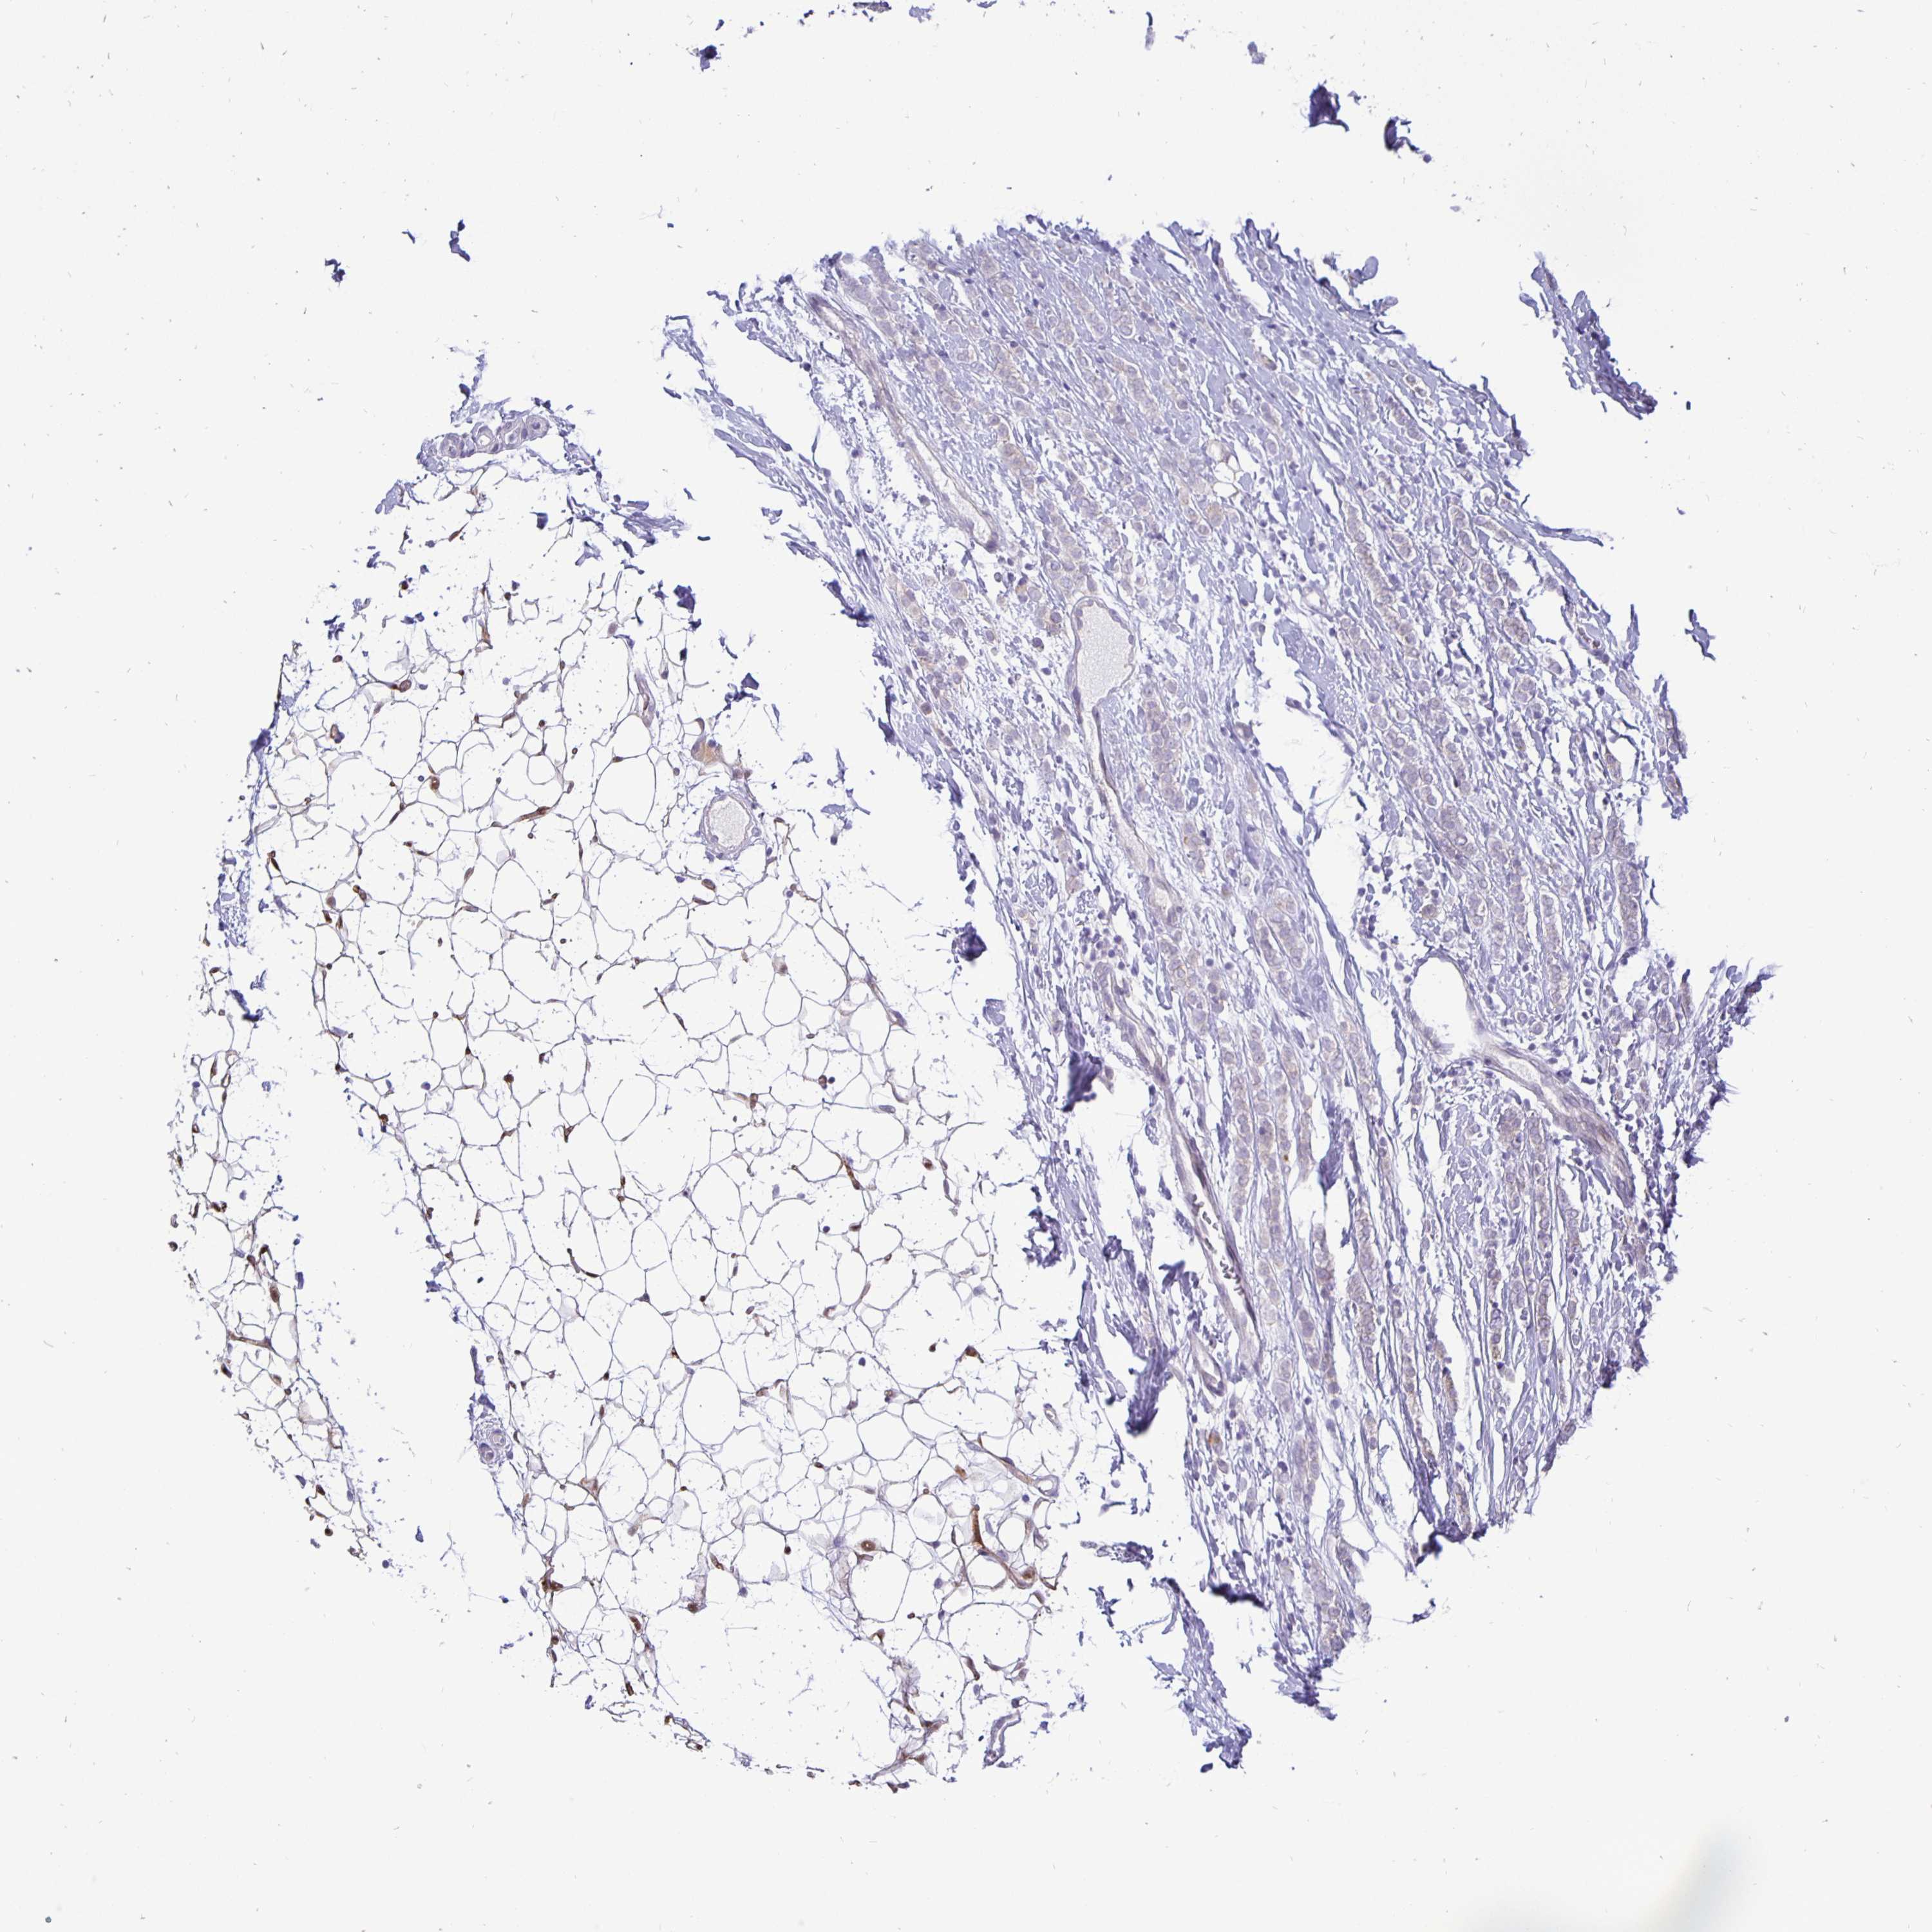

CANCER BREAST CANCER Show tissue menu

BRCA TCGA BRCA VALIDATION PROTEIN EXPRESSION

ANTIBODIES

AND

VALIDATION